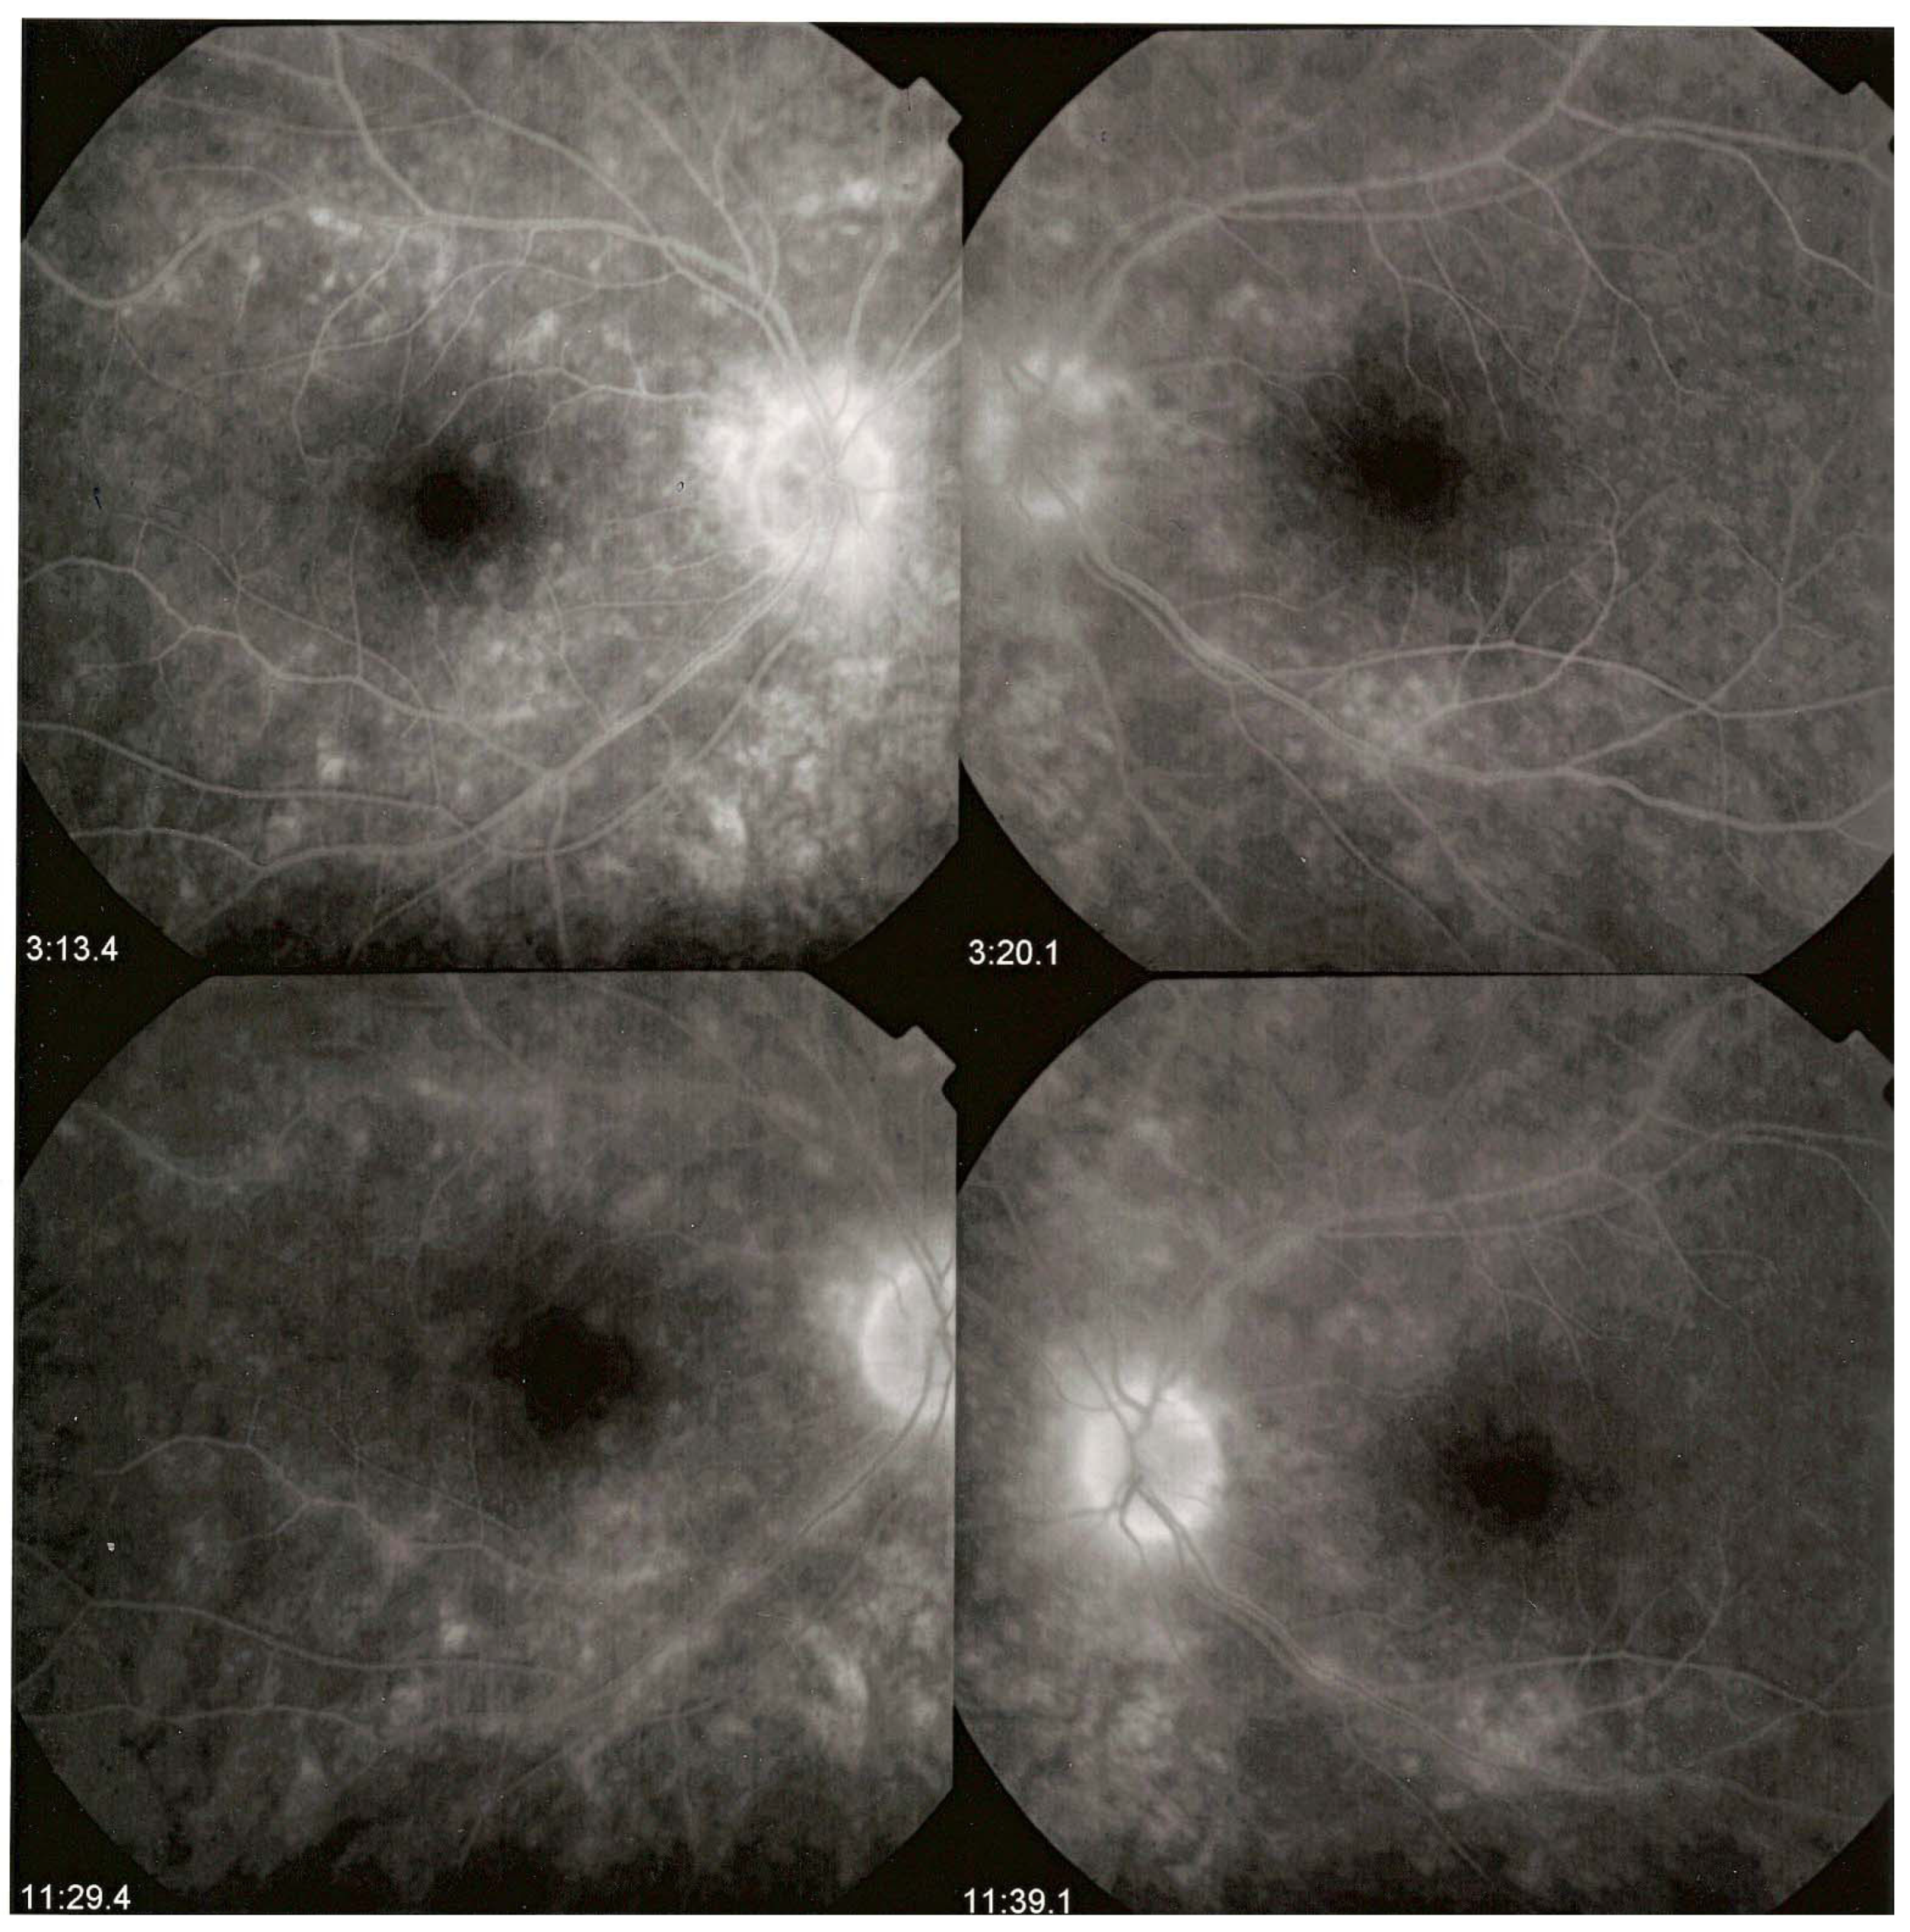

3.4.1. Fluorescein Angiography

3.4.3. Indocyanine Green Angiography (ICGA) Is Essential for Choroidal Involvement and Early Diagnosis